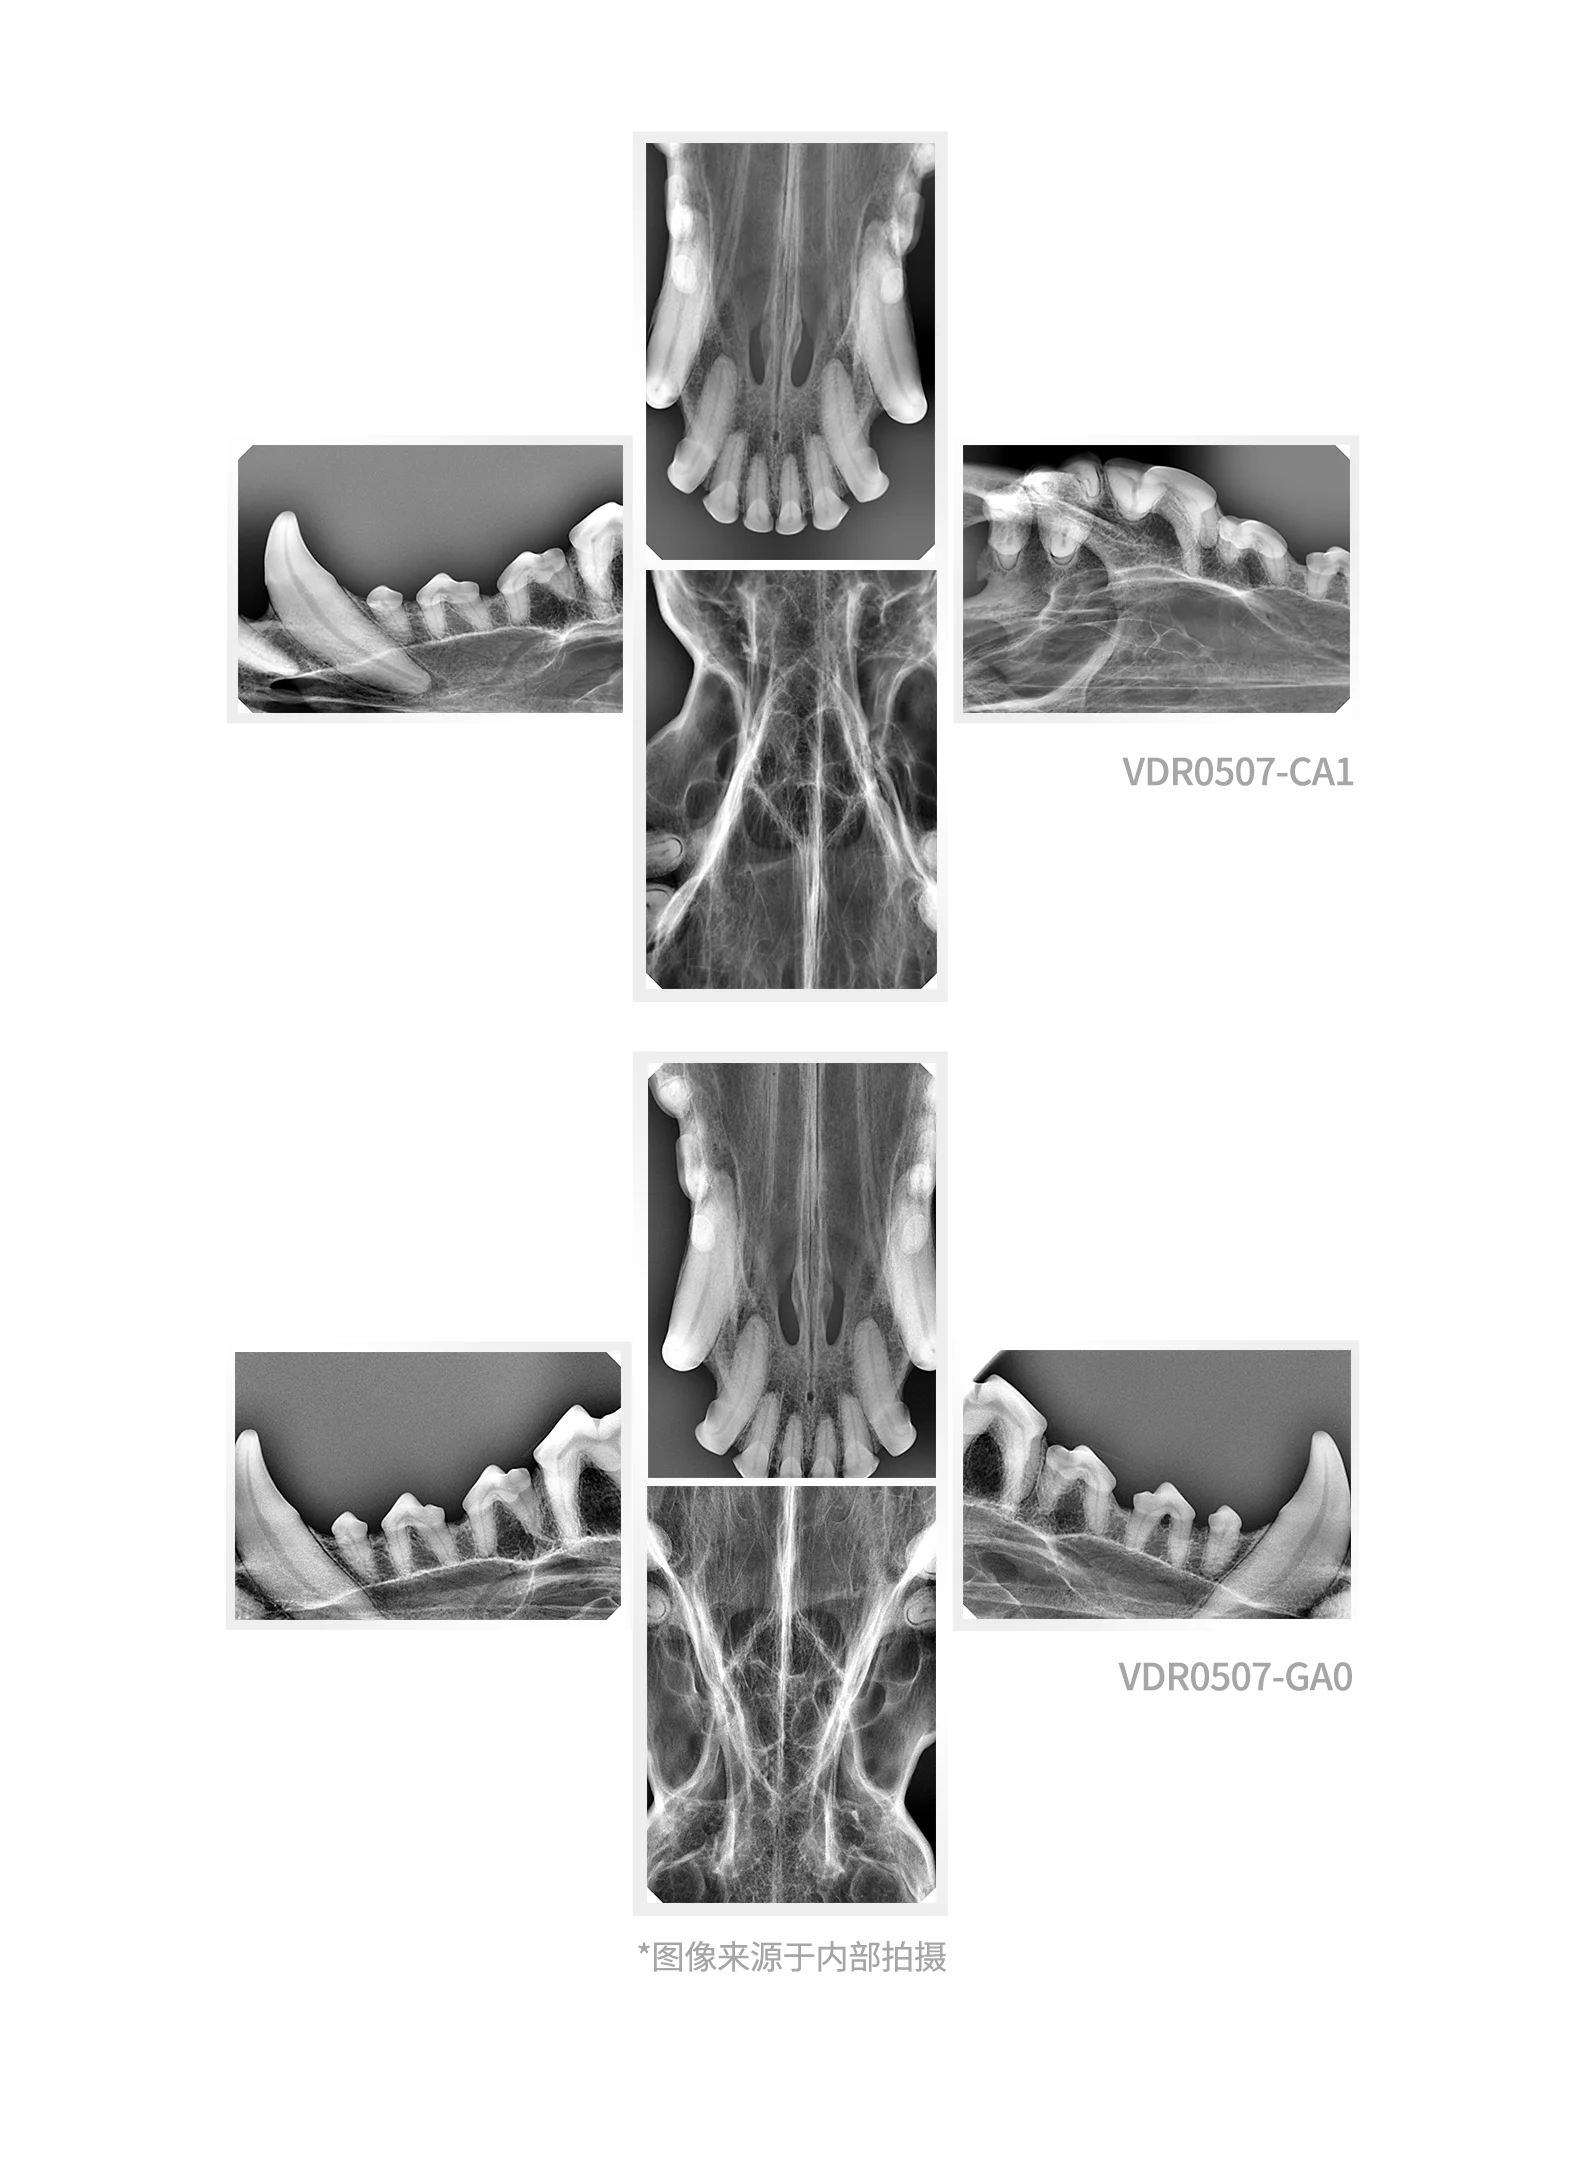

CE Approved Original HANDY Size 4 Dental X Ray Sensor Large Size Veterinary Sensor for Medium and Large Dogs

Model Number | VDR0507-GA0 |

Scintillator | CsI |

Chip type | CMOS APS |

Pixel Pitch (μm) | 9.19M(2524*3640) |

Line resolution | ≥ 10lp/mm (actual value) |

Effective area | 46.7*67.3mm |